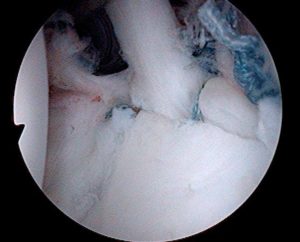

-Artroscopia:

Utilizando un equipo especial de alta tecnología, se visualiza la articulación a traves de una cámara y fibra optica, se colocan pequeños tubos especiales para introducir instrumental y suturas a la articulación y así poder reparar el tendón lesionado. Como ventaja, es mucho menor el daño a los músculos del hombro y la recuperación inicial es más rápida. Cirugía compleja que requiere un cirujano entrenado especialmente en esta técnica.